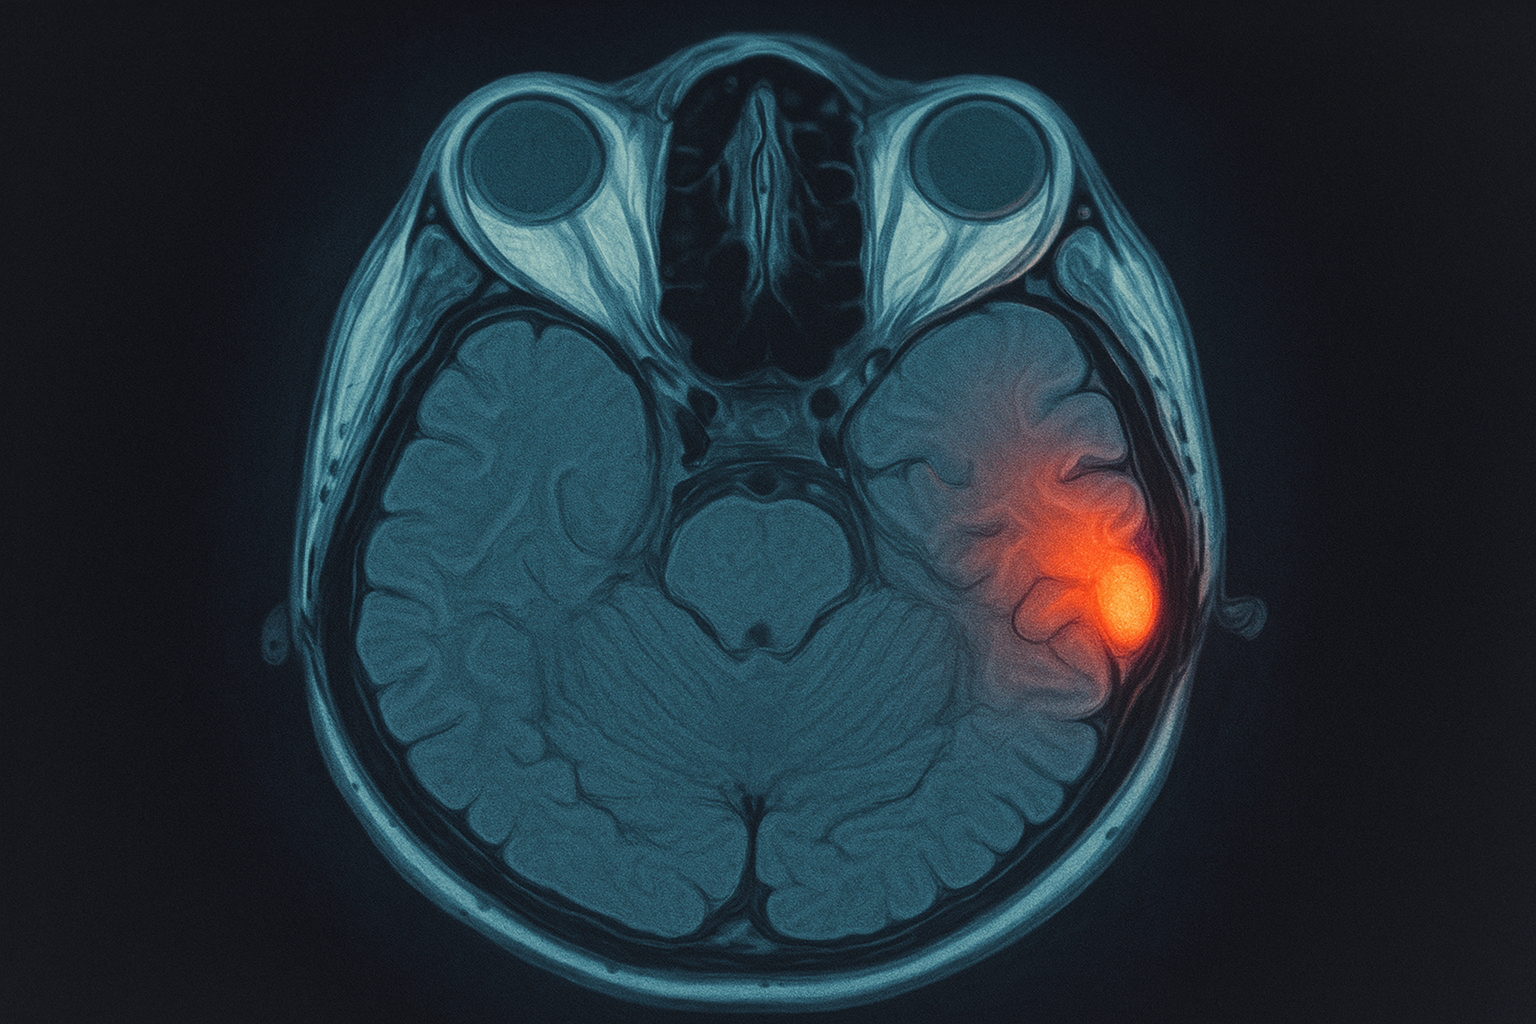

- MRI of the orbits and brain with gadolinium to look for optic nerve swelling and plaques that suggest multiple sclerosis (MS)